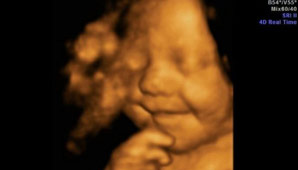

Buenos Aires, 17 de noviembre.- "Mi pareja Leighton y yo estábamos absolutamente sorprendidos. Pero esa ecografía fue sólo el principio, porque desde que nació no para de sonreír, incluso cuando está durmiendo", dijo Amy Cregg, la mamá, al Daily Mail.

La imagen se viralizó y comenzó a recorrer la web. Millones de personas en el mundo la vieron, se emocionaron y las agencias de publicidad no se quisieron quedar afuera. Su madre comenta que muchos la contactaron para usar la sonrisa.